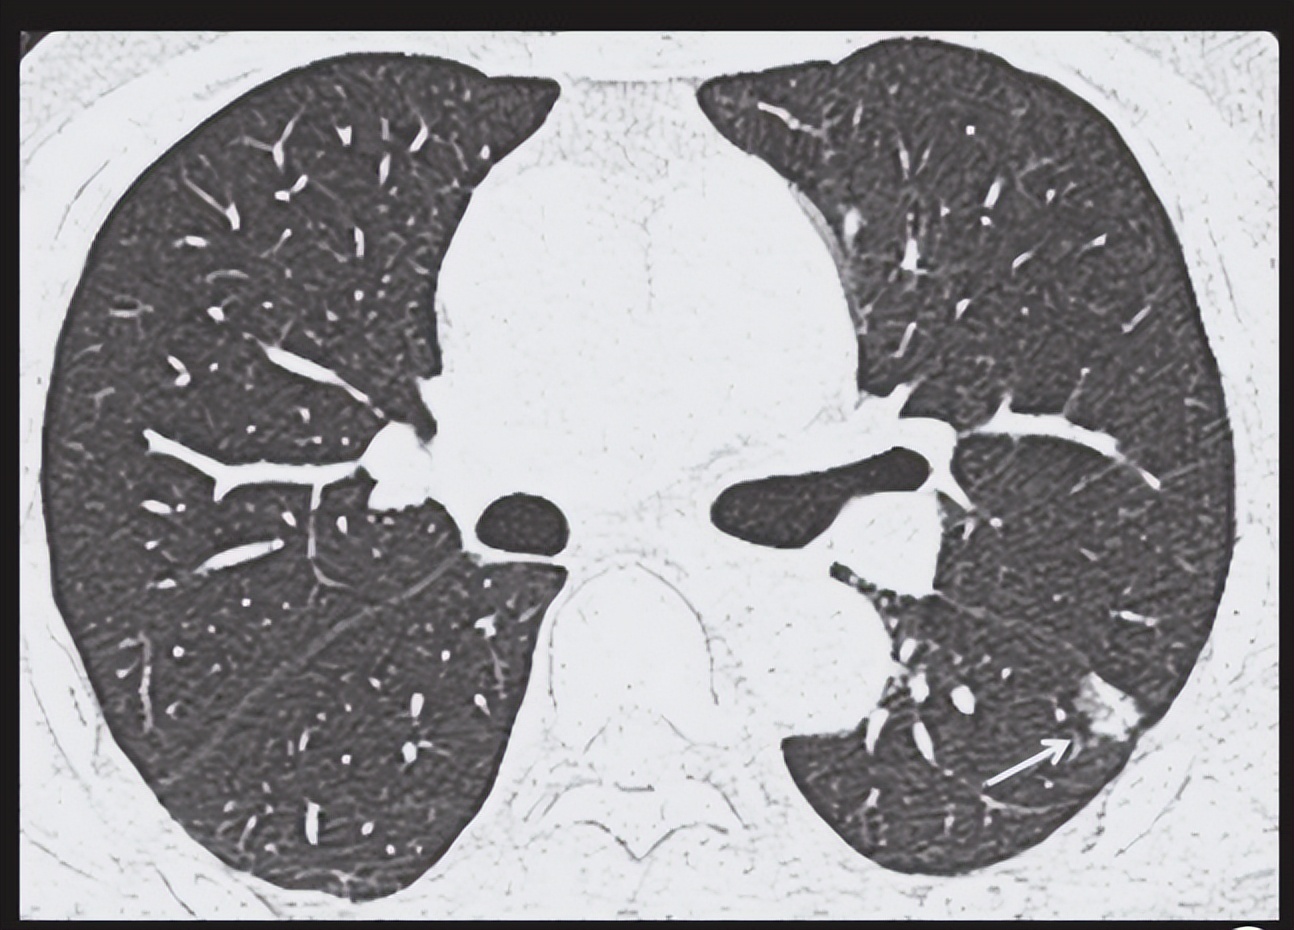

CT发现肺内密度增高影,但密度有不能掩盖病灶内支气管影和血管影的,称为磨玻璃影。如果病灶边界清楚,表现为结节状,呈圆形或类圆形,则为 磨玻璃结节 。

发现磨玻璃结节也别慌 ,应该说大部分-持续存在的磨玻璃结节是肺癌,但并不是说发现磨玻璃结节就等同于肺炎。碳末沉积、肺部炎症等一些良性病变也可能会出现磨玻璃结节。应进一步检查。